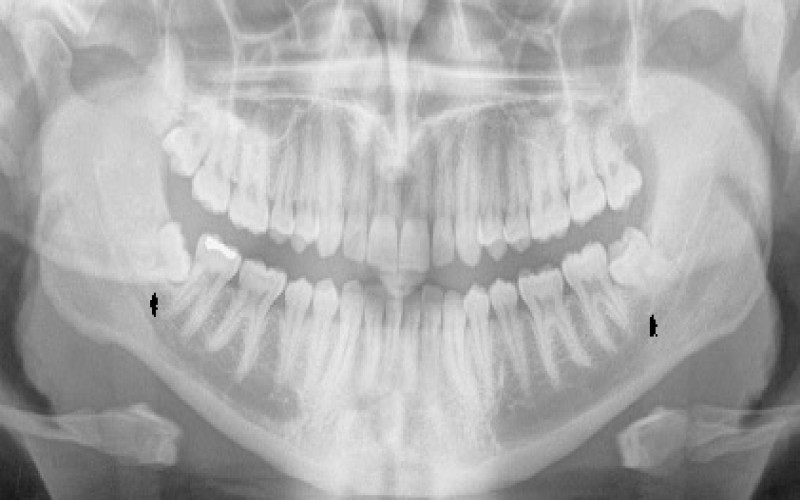

س: آیا باید قبل از جراحی عکس رادیولوژی بگیرم؟

ج: بله، عکس رادیولوژی به تشخیص دقیق موقعیت دندان و تصمیمگیری درباره نوع جراحی کمک میکند.